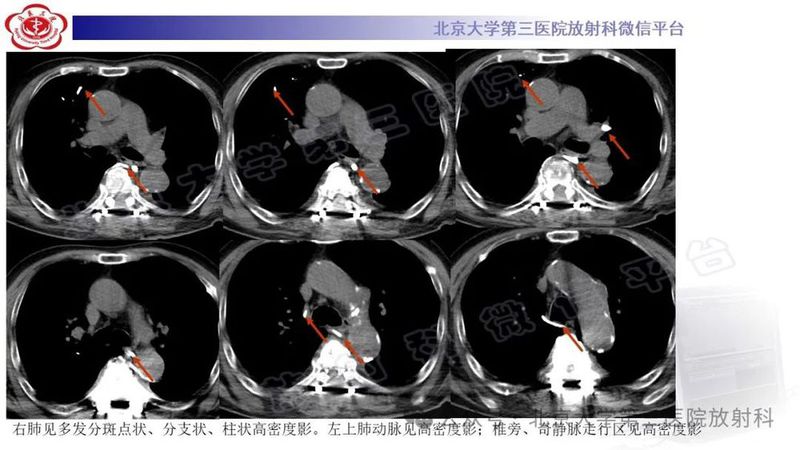

图文 | 骨水泥肺栓塞影像诊断

来源:北京大学第三医院放射科